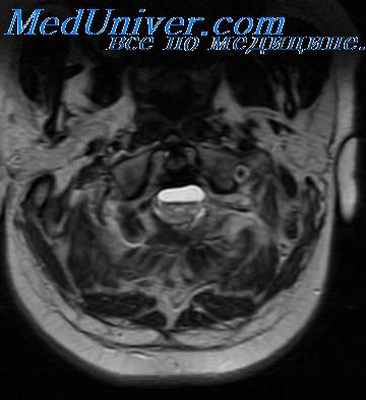

Для выявления кист и спаек оболочек мозга назначается КТ или МРТ. Может использоваться и рентгенография с контрастированием спинномозгового канала, но этот метод не столь информативен, как компьютерная или магнитно-резонансная томографии.

Самыми лучшими методами диагностики являются КТ головного мозга и МРТ . Может потребоваться люмбальная пункция. Эхо-энцефалография, электроэнцефалография и рентгенография черепа не такие информативные, но могут помочь в диагностике.

Пневмо-вентрикулография и энцефалография имеют при этом заболевании ограниченное применение, поскольку отогенный арахноидит локализуется, как правило, в задней черепной ямке. Энцефалография дает довольно убедительные симптомы при арахноидитах области большого мозга, когда определяется ограниченное расширение или частичное незаполнение воздухом субарахноидальных пространств с отсутствием асимметрии и деформации желудочков. При поражении задней черепной ямки энцефалография противопоказана. Вентрикулография как при туморах, так и при арахноидитах этой области может дать сходную картину расширения боковых и III желудочков (И. Я. Раздольский).

Плохое заполнение воздухом IV желудочка может наблюдаться при ограниченных арахноидитах, опухолях и абсцессах задней ямки (В. О. Калина). Любой вид пневмографии при выраженной гипертензии противопоказан. Диагноз иногда ставится во время операции. Обнаженная над областью поражения dura mater может выпячиваться (А. А. Бекрицкий, Ф. И. Шульмейстер).